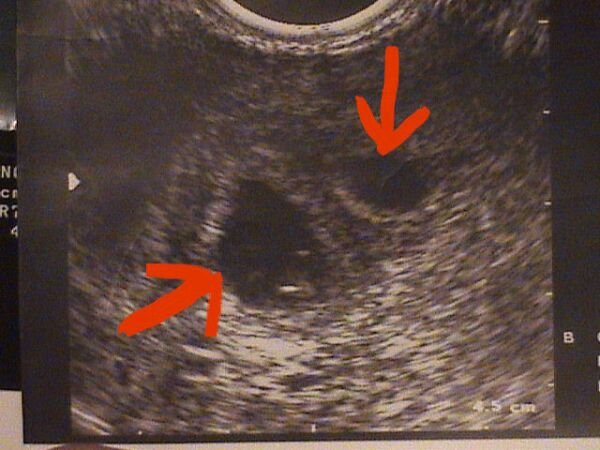

Dokihoz csak aznap jutottunk el, természetesen W.-hez mentünk és egy csomót izgultunk, hogy tényleg igaz-e, mert még mindíg nem mertük elhinni, de aztán megnyugtatott, hogy jó helyen van és tényleg ott van. Azon az UH- n még nem látszik csak egy pötty, úgyhogy nem is teszem fel, de a 21-i vizsgálatoon már szép petezsákot produkáltunk, benne Tökmag icipici teste is látszik a szikhólyaggal.

Kép